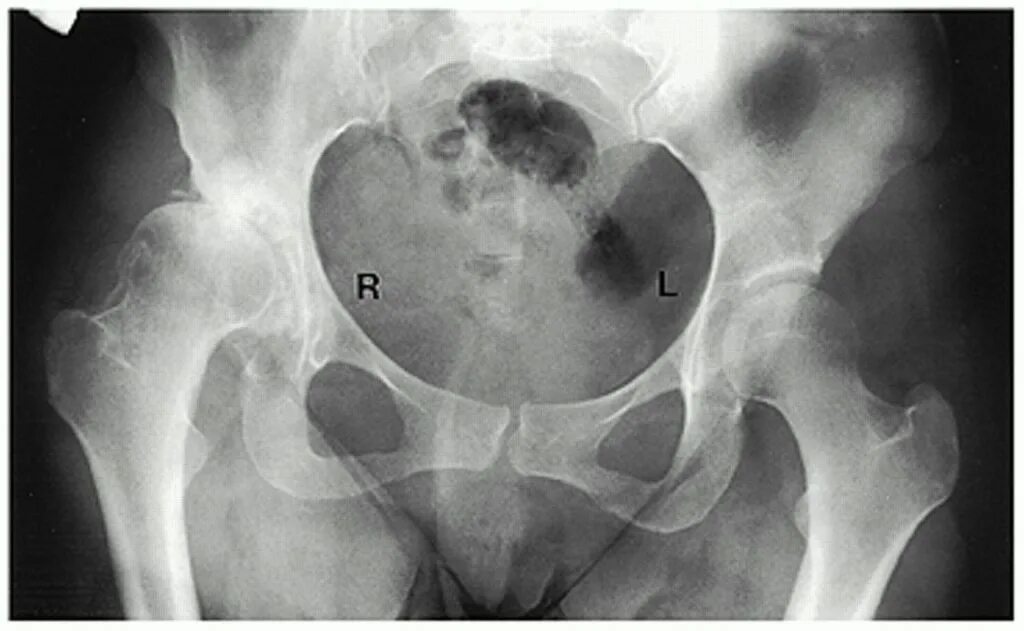

Как лечить синовит тазобедренного сустава